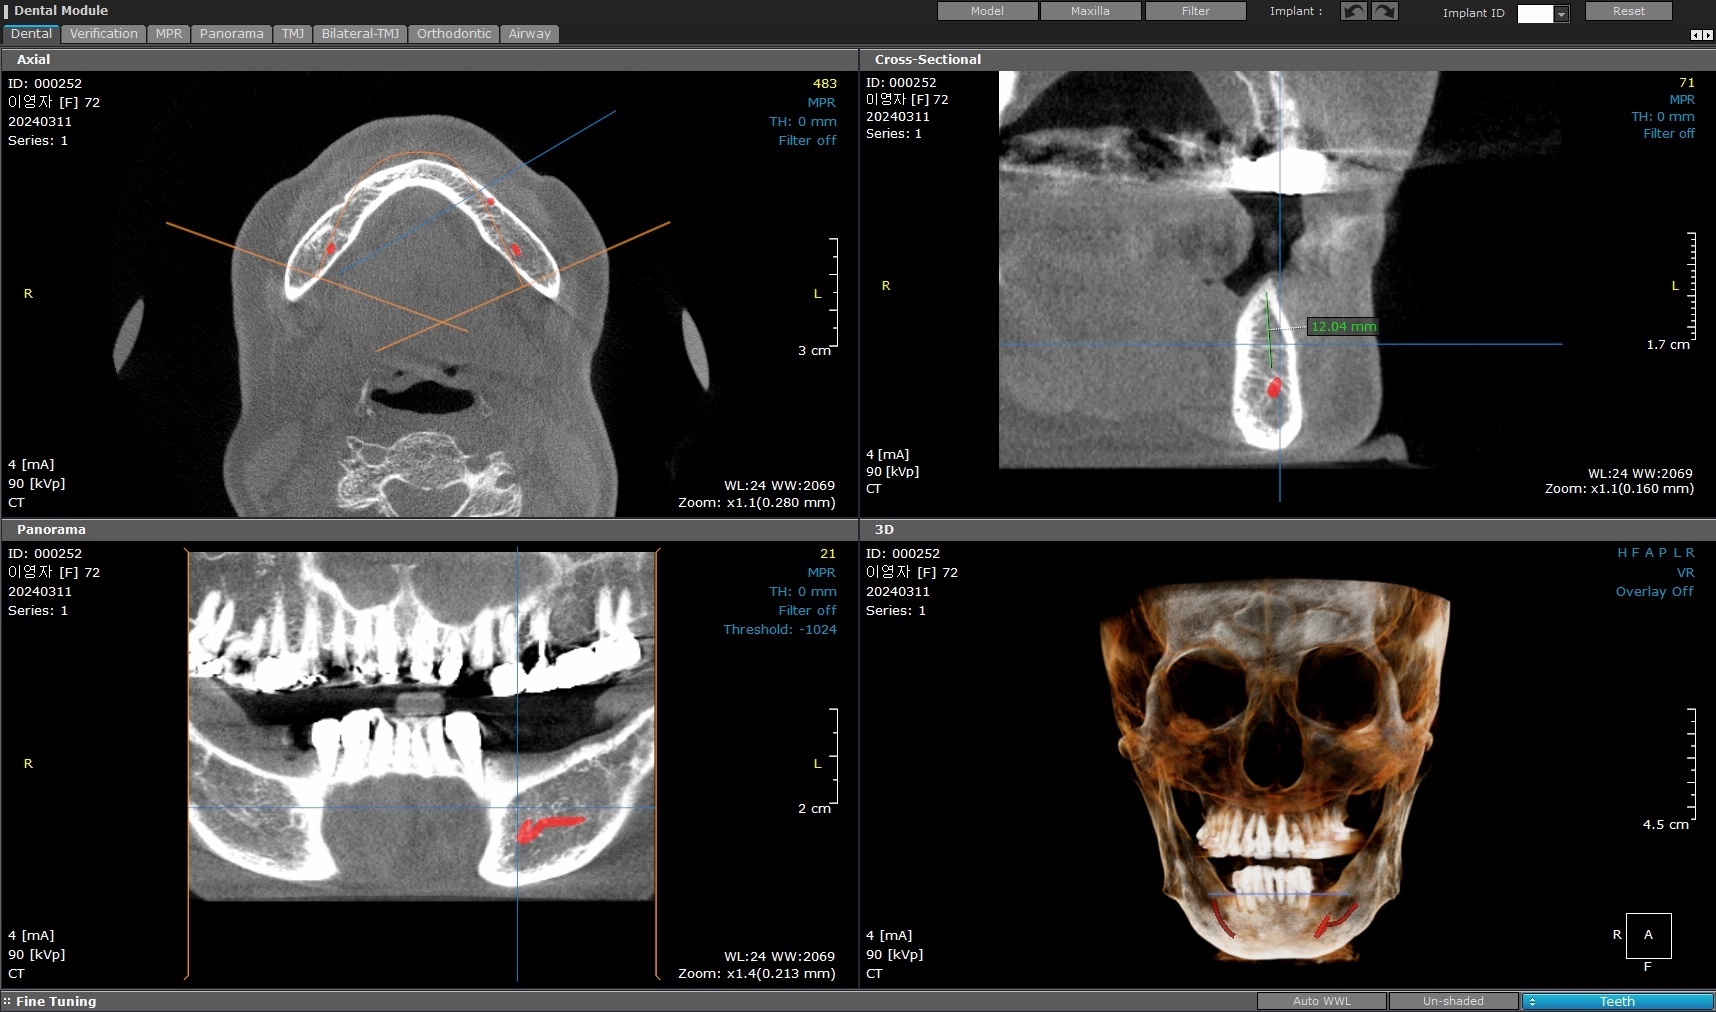

환자분의 엑스레이를 보면

‘칼릿지(Crest)’라고 불리는

잇몸뼈 부분이 거의 사라져 있었습니다.

CT를 분석해보면

정말 “뼈가 없다”라고 표현할 만큼

어려운 상황이었습니다.

이번 케이스에서도

그 기저골을 하나하나 찾아내

픽스쳐가 최대한

‘튼튼한 곳’을 잡을 수 있도록

각도를 미세하게 조정하며 식립했습니다.